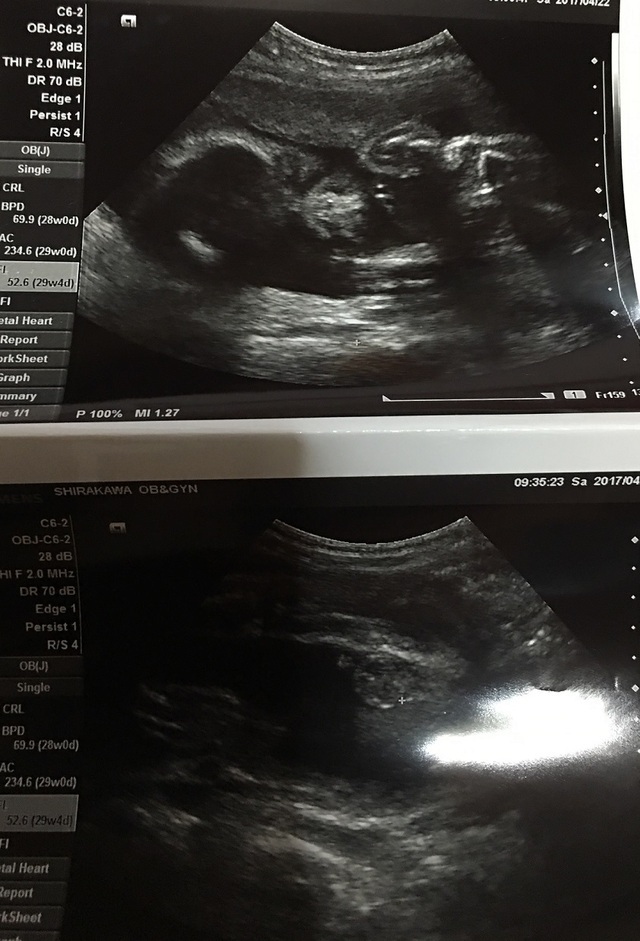

28週0日(28w0d・男の子)|ゆうきち0114 さん(28歳)

エコー写真撮影時のエピソード:

毎月の検診で顔が見れる!といつも楽しみでのぞむのですが…いつも手で顔を隠していて顔が見れずじまいでした。

この時初めて我が子の顔が写った!!と思いきや、なんだか鼻をほじってるようにも見え、なんだかクスッとなるような我が子との対面になりました。